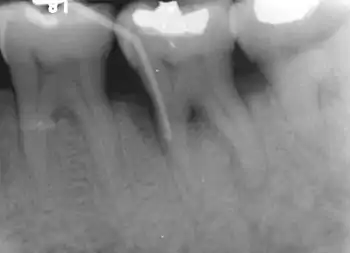

Evidence of furcal bone loss on #18 (lower left permanent second molar), along with a mesial vertical defect on the same tooth. The bent "stick" on the left of the tooth is a piece of gutta percha being used to trace the defect.